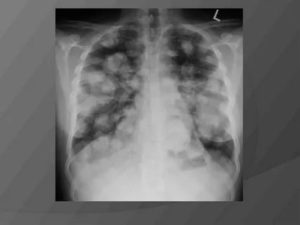

Метастазы в легком можно определить при помощи рентгенографии. Вторичные очаги онкологии на рентгеновских снимках представляются в узловой, смешанной и диффузной форме.

Узловые метастазы проявляются в единичной или множественной форме. Единичные, или солитарные образования, выглядят как округлые узелки, напоминающие первичный очаг онкологии. Чаще всего формируются они в базальной ткани.

Если вторичный генез носит псевдопневманическую форму, то на рентгене он отображается в виде тонких линейных образований.

При метастазировании в плевру на рентгеновских снимках видны крупные бугристые образования, в результате прогрессирования которых ухудшается состояние онкобольного и развивается легочная недостаточность.

- Рентгенография – исследует структуру тканей легких, выявляет затемнения, месторасположение метастаза и его размеры. Для этого делается два снимка – спереди и сбоку. На снимках множественные метастазы представляются в виде округлых узелков;

Метастазы в лёгких бывают разными по форме, ее определяют по рентгеновским снимкам:

- Очаговые метастазы, которые на рентгеновском снимке видны образования разного диаметра. Традиционно этот вариант метастазирования считается проявлением менее агрессивной злокачественной опухоли. При небольшом распространении более благоприятно протекают именно очаговые образования. Они как раз считаются преимущественно гематогенными, то есть занесёнными кровью.

- Инфильтративные метастазы, когда опухолевые клетки расползаются по эпителиальной выстилке альвеол, что на рентгенограмме проявляется в виде сетки или разной формы затемнений. Такой вариант традиционно считают вариантом более агрессивной опухоли — агрессивные по течению меланомы и саркомы дают преимущественно очаговые, а не инфильтративные метастазы в лёгких. Эти вторичные проявления относят к лимфогенным.

- Смешанные метастазы — сочетание очаговых и инфильтративных «теней» в лёгких — частое явление в клинической практике.